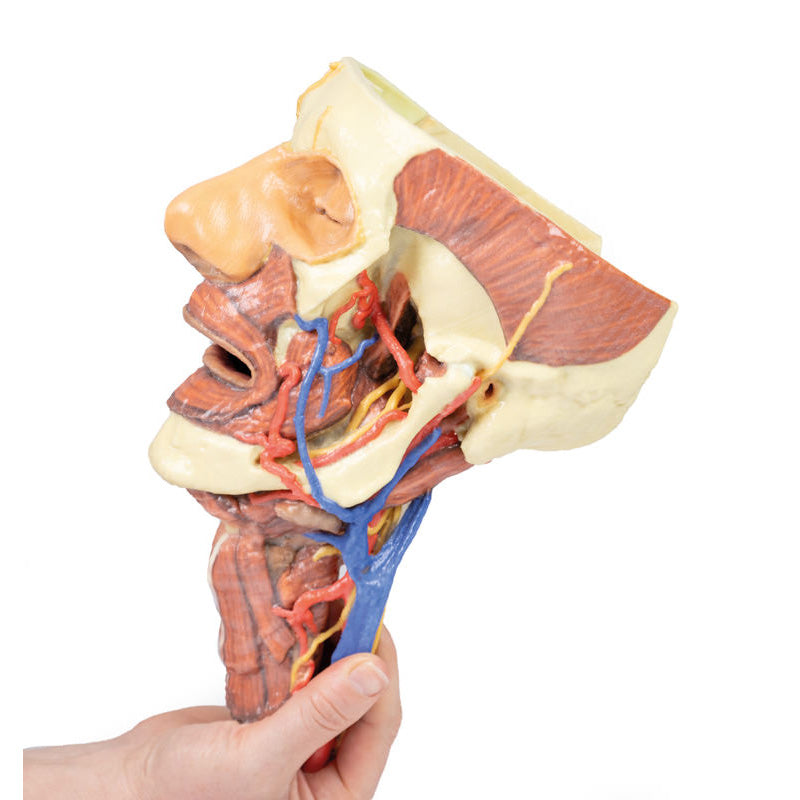

The neck: The musculoskeletal portion of the neck have been removed to display the pharynx posteriorly, the larynx anteriorly, and the neurovascular bundles laterally. The suprahyoid and infrahyoid muscles can be seen on the neck, as well as the cricothyroid muscle.

When looking up the length of the trachea from below, the vocal folds are visible. The hypoglossal nerve can be seen winding around the lateral surface of the external carotid artery and the external branch of superior laryngeal nerve is seen descending in the neck. The internal jugular vein, the common carotid artery and its bifurcation into external and internal carotid arteries are clearly seen on both left and right. The vagus nerve in the carotid sheath is also visible. The ansa cervicalis is visible emerging below the digastric muscle and descending on the surface of the internal jugular vein. The internal branch of the superior laryngeal nerve can be seen below the superior thyroid artery on the left. The superior thyroid artery branching from the external carotid artery is seen descending in the anterior neck. The internal branch of the superior laryngeal artery is visible on the left piercing the thyrohyoid membrane above the inferior constrictor where this muscle is attached to the hyoid bone.

Posterior view of the pharynx: The superior, middle and inferior pharyngeal constrictors are indicated on the pharynx wall. The oesophagus can be identified emerging from the lower end of the pharynx. The posterior horn of the hyoid bone acts as a useful landmark. The carotid sheath seen from behind clearly shows the vagus nerve and its pharyngeal branches on the left. The recurrent laryngeal nerve is briefly visible on the left lying medial to the inferior thyroid artery. The occipital arteries are visible as they curve around the mastoid process. The vertebral arteries are seen either side of the brainstem as they enter the foramen magnum. The cerebellum has been removed to allow the fourth ventricle to be exposed. The cut surfaces of the cerebellar peduncles are clearly visible. A large portion of the posterior inferior cerebellar artery on the right is still visible as it winds around around the brainstem.

The neck: The musculoskeletal portion of the neck have been removed to display the pharynx posteriorly, the larynx anteriorly, and the neurovascular bundles laterally. The suprahyoid and infrahyoid muscles can be seen on the neck, as well as the cricothyroid muscle.

When looking up the length of the trachea from below, the vocal folds are visible. The hypoglossal nerve can be seen winding around the lateral surface of the external carotid artery and the external branch of superior laryngeal nerve is seen descending in the neck. The internal jugular vein, the common carotid artery and its bifurcation into external and internal carotid arteries are clearly seen on both left and right. The vagus nerve in the carotid sheath is also visible. The ansa cervicalis is visible emerging below the digastric muscle and descending on the surface of the internal jugular vein. The internal branch of the superior laryngeal nerve can be seen below the superior thyroid artery on the left. The superior thyroid artery branching from the external carotid artery is seen descending in the anterior neck. The internal branch of the superior laryngeal artery is visible on the left piercing the thyrohyoid membrane above the inferior constrictor where this muscle is attached to the hyoid bone.

Posterior view of the pharynx: The superior, middle and inferior pharyngeal constrictors are indicated on the pharynx wall. The oesophagus can be identified emerging from the lower end of the pharynx. The posterior horn of the hyoid bone acts as a useful landmark. The carotid sheath seen from behind clearly shows the vagus nerve and its pharyngeal branches on the left. The recurrent laryngeal nerve is briefly visible on the left lying medial to the inferior thyroid artery. The occipital arteries are visible as they curve around the mastoid process. The vertebral arteries are seen either side of the brainstem as they enter the foramen magnum. The cerebellum has been removed to allow the fourth ventricle to be exposed. The cut surfaces of the cerebellar peduncles are clearly visible. A large portion of the posterior inferior cerebellar artery on the right is still visible as it winds around around the brainstem.